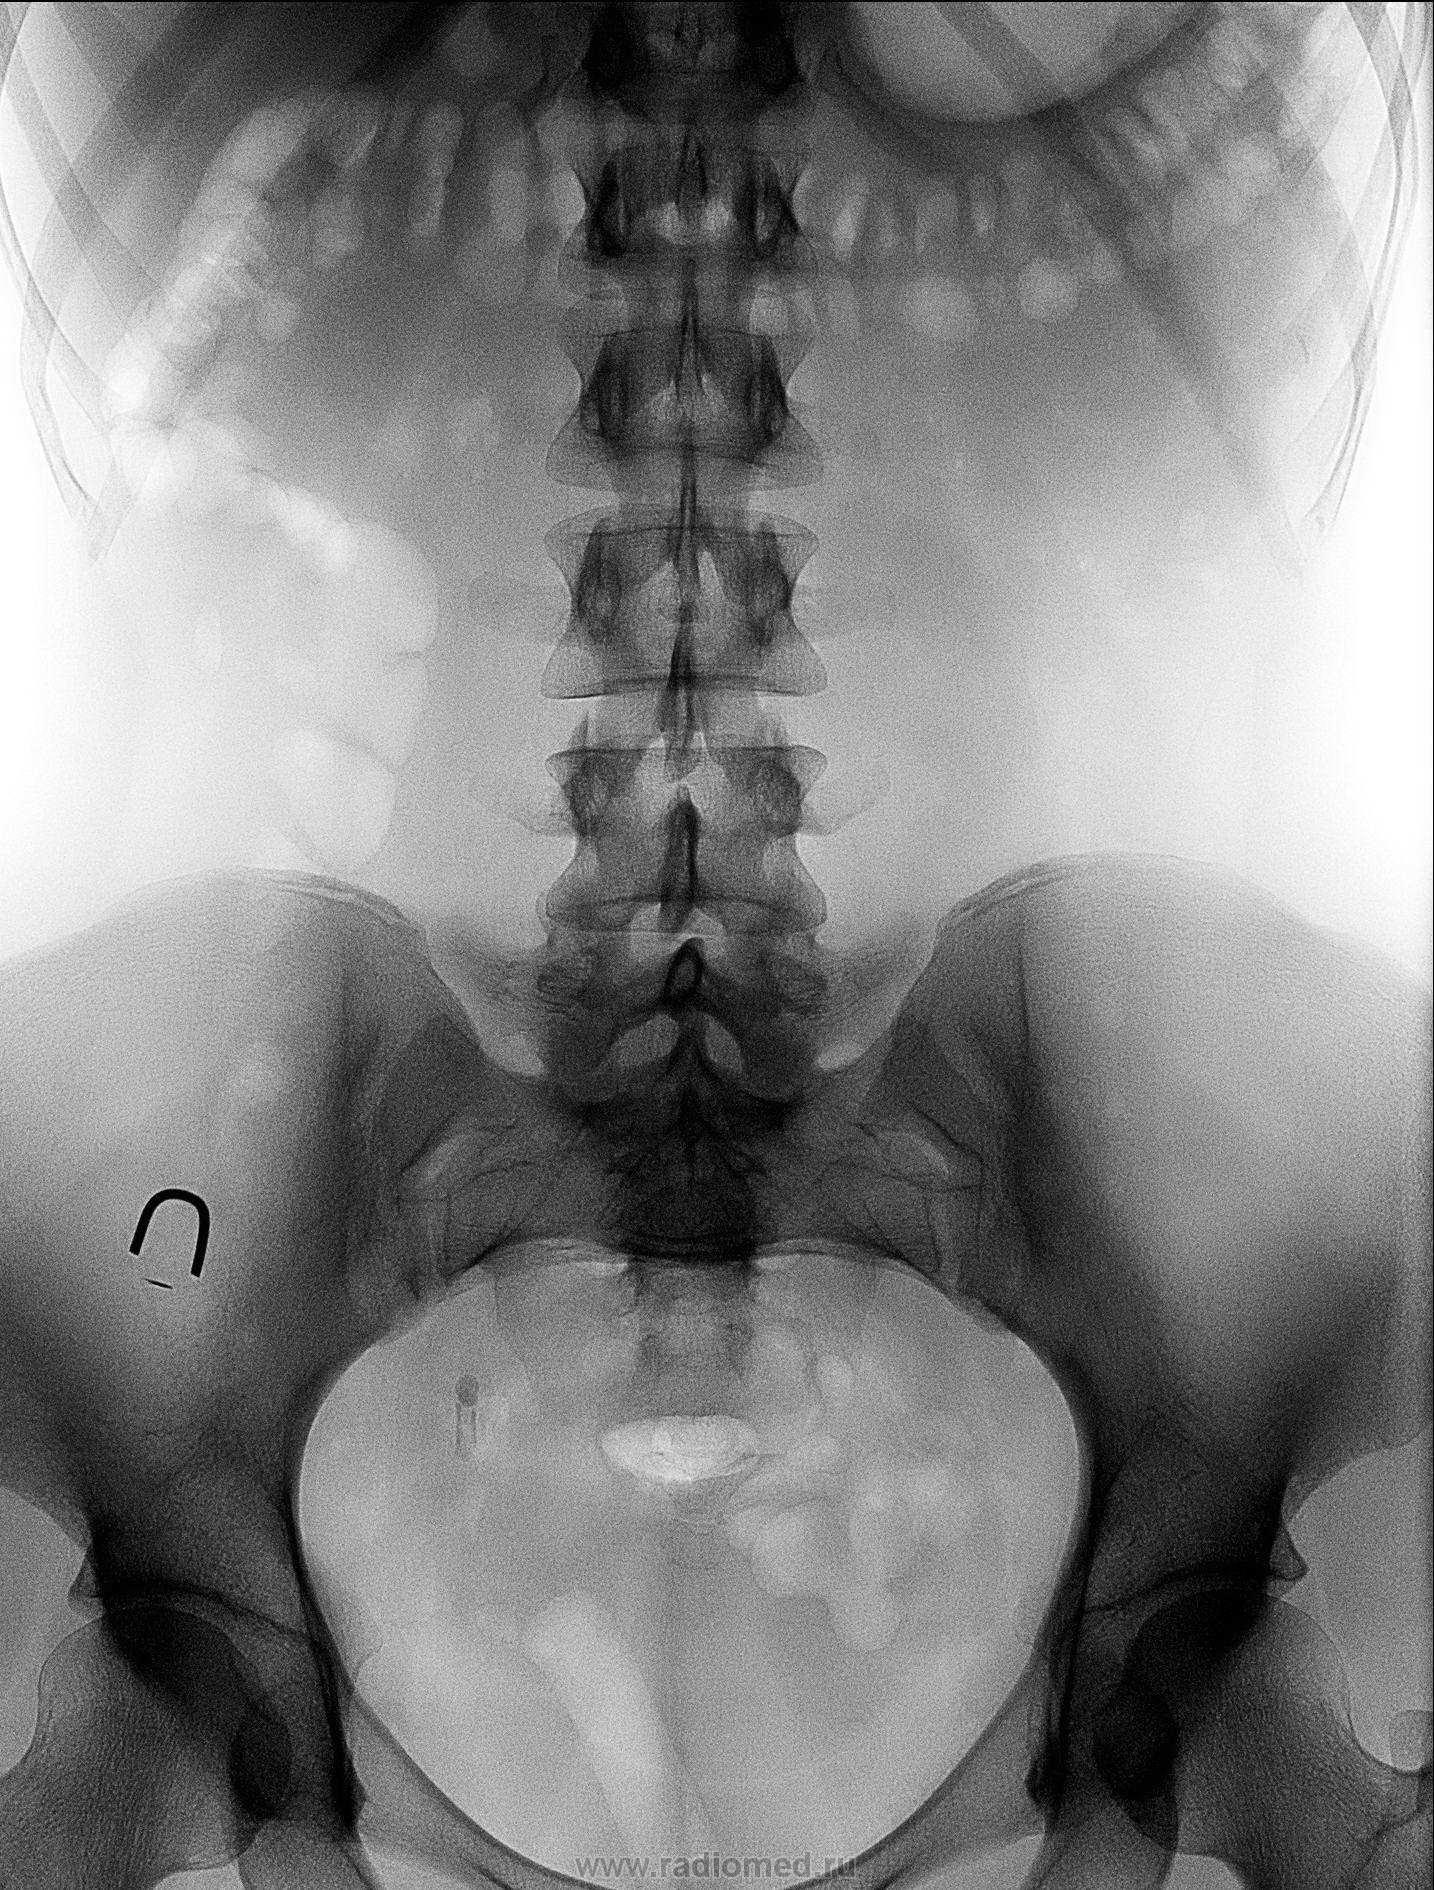

Пациентка с ноющей болью в поясничном отделе позвоночника, после проведения УЗИ(расширение ЧЛС справа) направлена к нам:

На урограммах чётко видно, конкремент н/3 правого мочеточника с гидронефрозом правой почки. А демонстрирую я это не прото так, чуть ниже конкремента идёт отложение по стенке мочеточника, я так понимаю уратов??? Ваше мнение?

Итак, в дистальной трети правого мочеточника визуализируется конкремент (рентгеноположительный), неоднородной структуры, с отдельными "более плотными" включениями.

А почему на последнем снимке почек в правой лоханке горизонтальный уровень контраста?

Описание операции: Уретра проходима свободно, в полости мочевого пузыря без патологии, слизистая обычного цвета. Устья мочеточников в типичном месте, щелевидные, не изменены. В правое усттье введен уретерореноскоп, на 7-8 см обнаружен конкремент 1х1,5 см размерами, фрагментирован пневматическим литотриптором, фрагменты низведены в плсть мочевого пузыря петлей Дормиа. Ретроградная пиелография - просвет мочеточника и полостная система почки расширены, теней уроконкрементов, дефектов наполнения нет. Под R-контролем по струне проводнику в правый мочеточник установлен мочеточниковый стент типа "pig tail" №6Ch, 24 см. Уретрально установлен катетер Фолея № 20 Ch, баллон 15 мл.